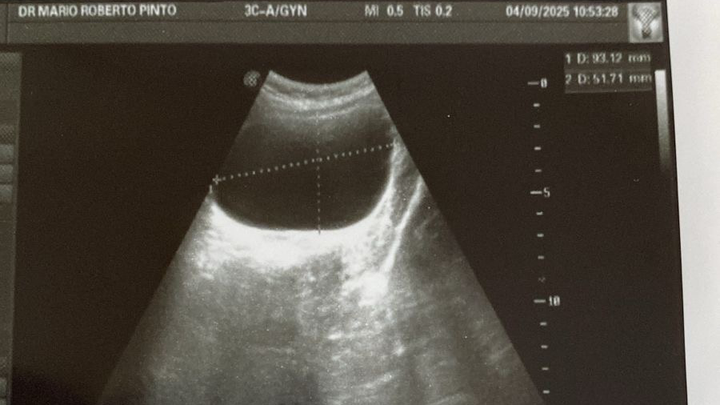

My name is Augusto WahLung, and all my life I've worked as an English as a Second Language teacher. My life changed when I tried to start my own business and failed; this led me to acquire a huge debt, and at this moment, I need help to cover the medical expenses of a surgery for my daughter Andrea. She currently has a cyst on one of her ovaries and must undergo surgery as soon as possible to save her ovary. In a few months, she will need a second surgery to remove a plate that connects one of the bones in her left leg. This plate must be removed so that her bone can grow normally.